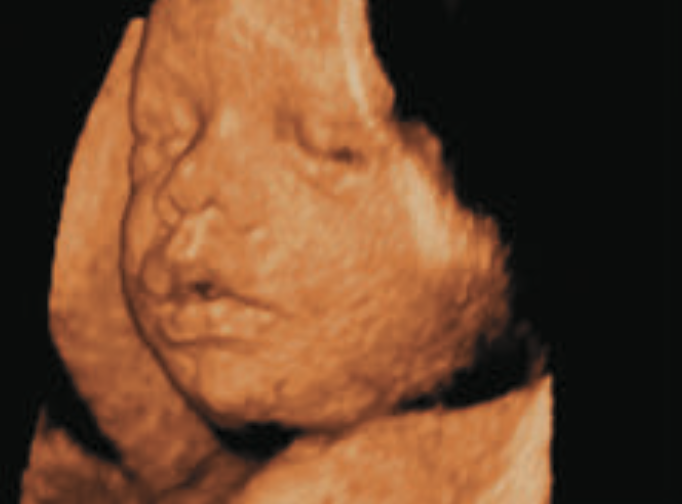

Fonte: Giphy

As ondas sonoras com frequências muito elevadas e comprimentos de onda muito pequenos, chamadas de ultrassom, percorrem o corpo humano, e os “ecos” oriundos do interior do organismo são usados para criar uma imagem. Para um ultrassom com frequência igual a 5 Mhz = 5 x \(10^6\) Hz, o comprimento de onda na água (o constituinte principal do corpo humano) é igual a 0,3 mm, e características com dimensões até essa ordem de grandeza podem ser discernidas na imagem

Fonte: Sears & Zemansky